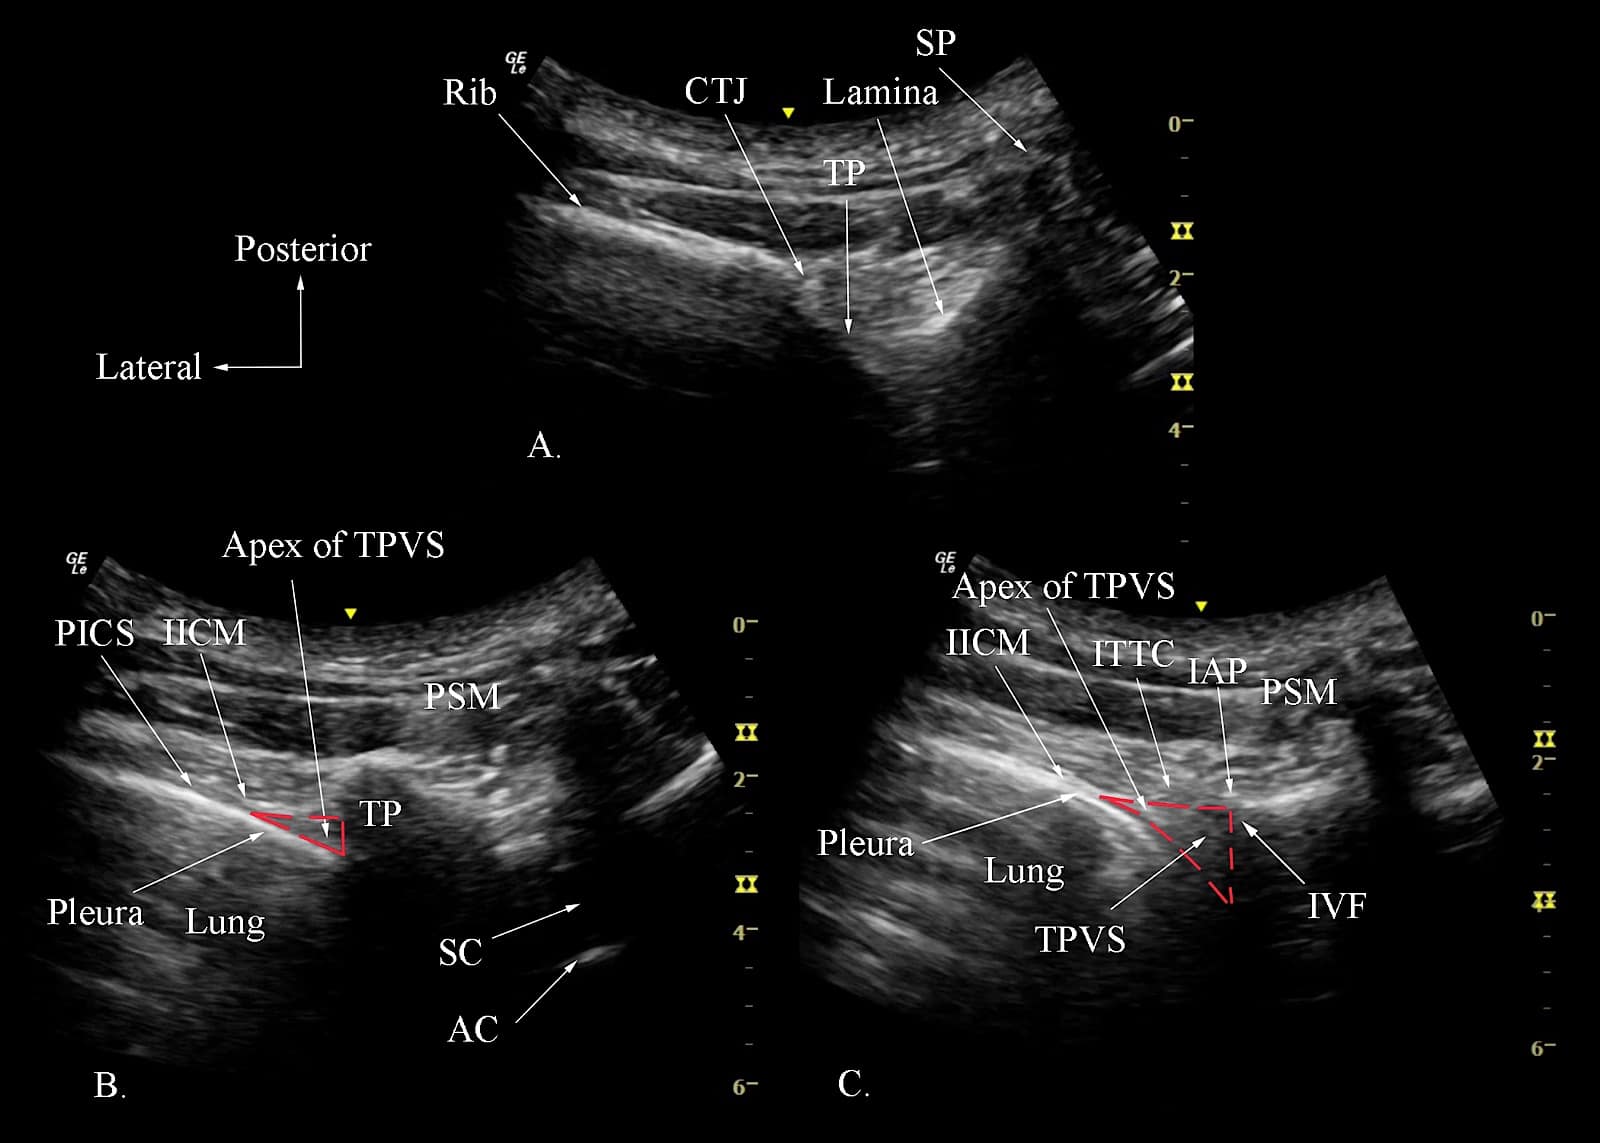

Figure 9. Transverse sonograms of the thoracic paravertebral region with the ultrasound beam being insonated at the level of the transverse process-rib complex (position 1 in Figure 10A) at the transverse process level, (position 2 in Figure 10B), and at the inferior articular process (IAP) level (position 3 in Figure 10C).

SP = spinous process, TP = transverse process, CTJ = costotransverse junction, PSM = paraspinal muscles, TPVS = thoracic paravertebral space, IICM = internal intercostal membrane, PICS = posterior intercostal space, SC = spinal canal, AC = anterior complex, ITTC = intertransverse tissue complex, IVF = intervertebral foramen

Reproduced with permission from the Department of Anesthesia and Intensive Care, The Chinese University of Hong Kong, Faculty of Medicine, www.aic.cuhk.edu.hk/usgraweb.

Step 1: Transverse scan at the transverse process-rib complex level. The transducer is positioned 2-3 cm lateral to the midline (spinous process) at the target vertebral level, in the transverse plane, and over the rib and costotransverse articulation (Figure 10, position 1, red box). The hyperechogenic outlines of the spinous process, lamina, TP, costo-transverse junction and the rib with their corresponding acoustic shadows are clearly delineated from a medial to lateral direction (Figure 9A). The posterior angulation of the TP of the thoracic vertebra is also easily recognized (Figure 9A). This contrasts with the TP of the lumbar vertebra, which is at right angles to the vertebral body. This ultrasound window does not lend itself to visualizing the paravertebral anatomy because the acoustic shadow of the TP-rib complex completely obscures the TPVS (Figure 9A). Therefore, it is used more as a starting point for the subsequent steps in the scan sequence.

Step 2: Transverse scan at the transverse process level. From position 1, gently slide the transducer caudally until the acoustic shadow of the rib is no longer visible (Figure 10, position 2, blue box), and the hyperechogenic outline of the lamina and TP with their acoustic shadow are visualized (Figure 9B).11,62,63 Lateral to the TP, one can define the IICM posteriorly and the hyperechogenic pleura and lung anteriorly. Interposed between the two is the hypoechoic apical part of the TPVS (Figure 9B).9,11,12 The PICS may also be visualized in continuity with the apex of the TPVS laterally (Figure 9B).

Step 3: Transverse scan at the inferior articular process level. Finally, suppose one gently slides or tilts the transducer caudally from position 2 (Figure 10, position 3, green box). In that case, the acoustic shadow of the lamina and transverse process disappear and the hyperechogenic IAP (Figure 9C) is now visualized medially.11,62,63 This acoustic window represents the transverse-intertransverse view of the TPVS.11,62,63 As in the sonogram at the level of the TP (Position 2, Figure 9B), the SCTL, parietal pleura, lung and the apical part of the paravertebral space are clearly delineated (Figure 9C).11,62,63 However, the area of the acoustic shadow at the level of the IAP is significantly less than that at the level of the TP. As a result, one can visualize the majority of the TPVS in this view (Figure 9C).11,62,63 On a different note, the same transverse ultrasound window at the IAP level can be utilized to visualize the retro-SCTL space by gently pivoting the lateral end of the transducer caudally and performing an ITPB at the retro-SCTL space.29,57 Currently, limited published data are describing the use of a transverse scan at the level of the IAP for USG TPVB.11,12,63